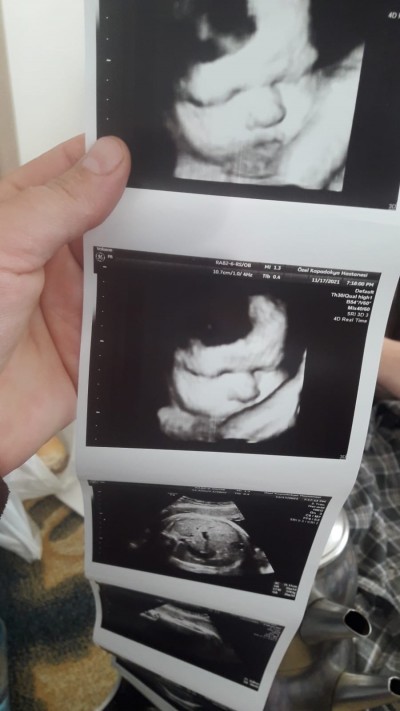

9 aylik hamilelik ultrason resmi cinsiyet tahmini yapar mısınız

Gebelik haftası 39

Attim resim

Attim simdi resim

Erkek bence :) ama bebektir yani erkek de olsa kiz da olsa aynı gorunur yüz şekli bebiş yani bebek yüzlü adı üstündee bebeeeeekkk :)))

Çene şeklinden ayırt ediliyormuş

Kiz demis doktor

Kız çünkü yüzü kibar.. Erkek bebeklerinki biraz daha kaba.. Çünkü bizimki kaba

Valla cinsiyeti anlamadım ama kesin olan bişey var ki coookk tatlı bir bebiş geliyor Allah sağlıkla kucağınıza almayı nasip etsin

Kiz bence kiza benzettdim

Ya ne güzel yüzü çıkmış benim hiç yok böyle yüzünü hiç göremedik

Kacinci ayinda yüz şekli boyle gorunuyor ultrasonda

erkek bu canım

Bebegin yuzunden cinsiyet belli olmaz ki

Çene seklini kas ettim